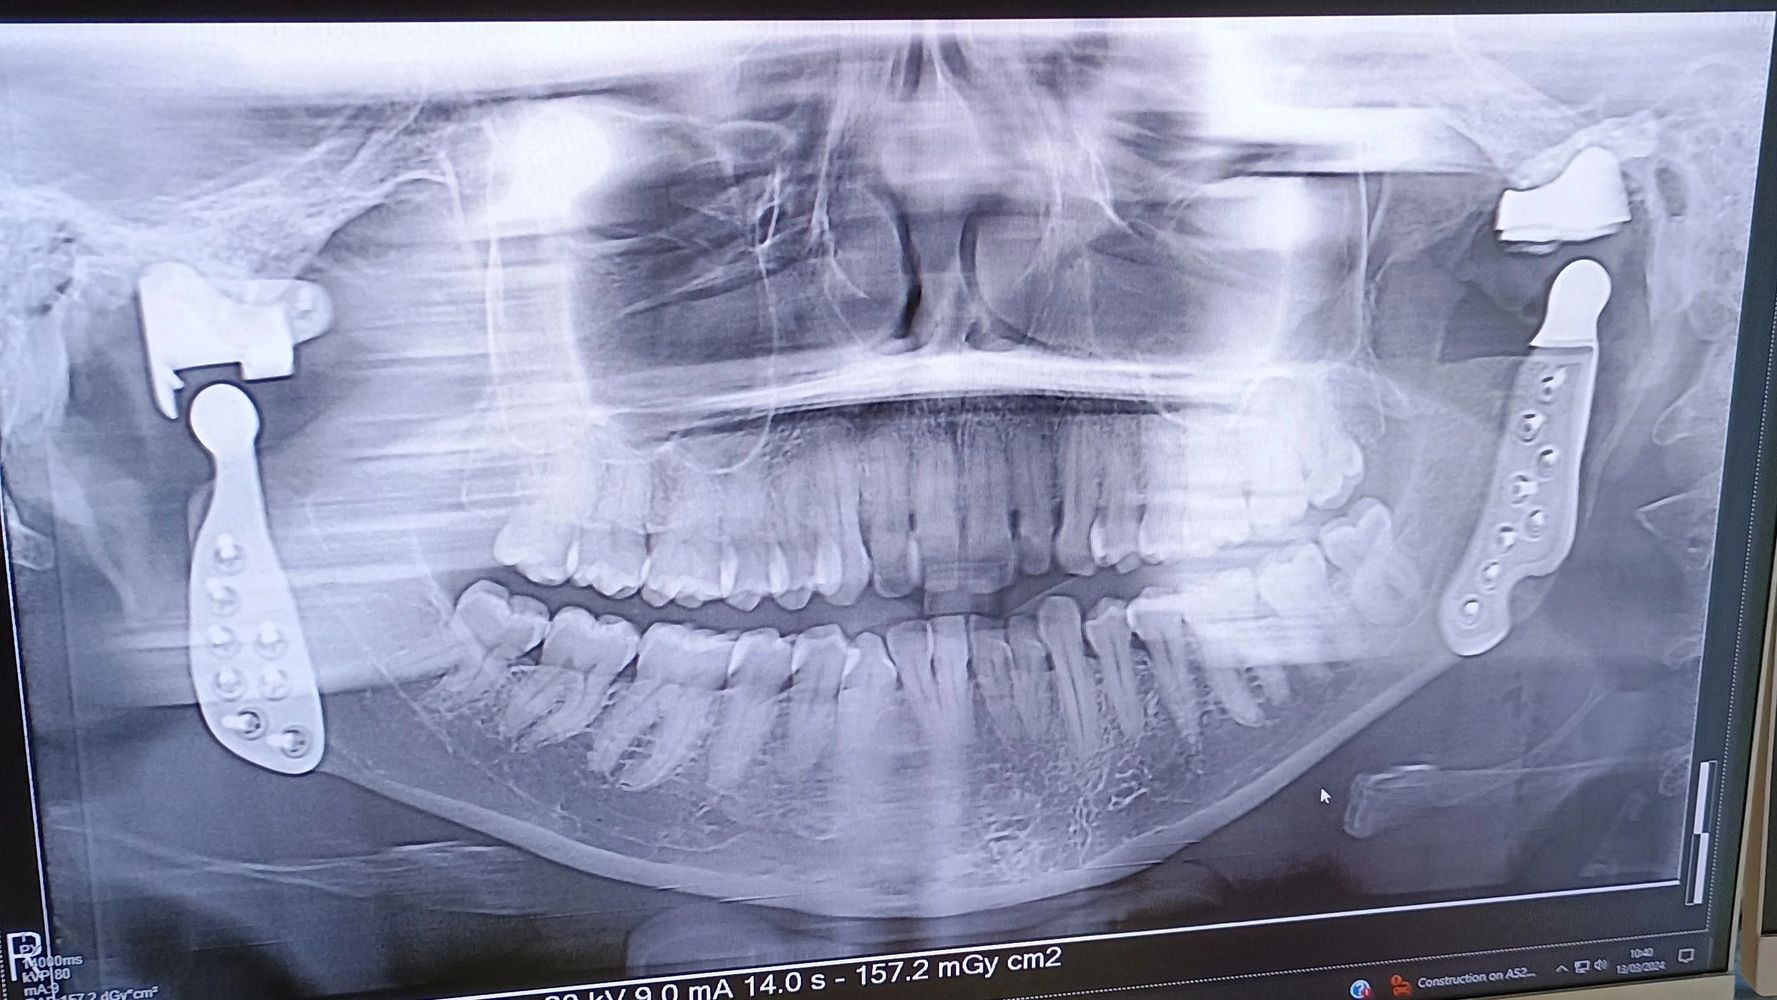

I have multiple long term health conditions; Antiphospholipid Syndrome (APS), Raynaud's, Hypermobility Spectrum Disorder (HSD), Osteoarthritis (in multiple joints) and Hemiplegic Migraines with Aura. I am the proud owner of Bilateral Titanium Temporomandibular Joint (TMJ) Replacements (right side replaced in February 2022 and left side replaced in March 2024). Along with various allergies and intolerances!